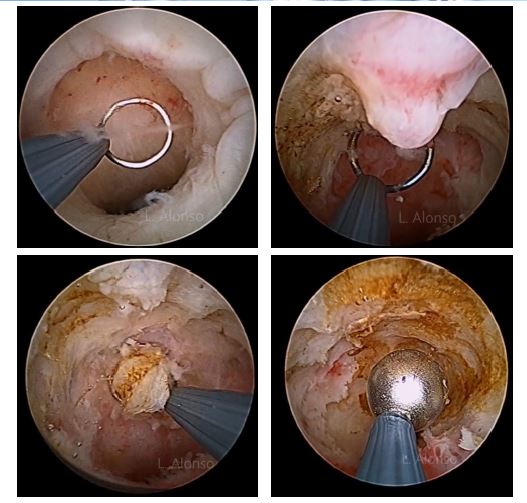

Category: cesarean scar defect